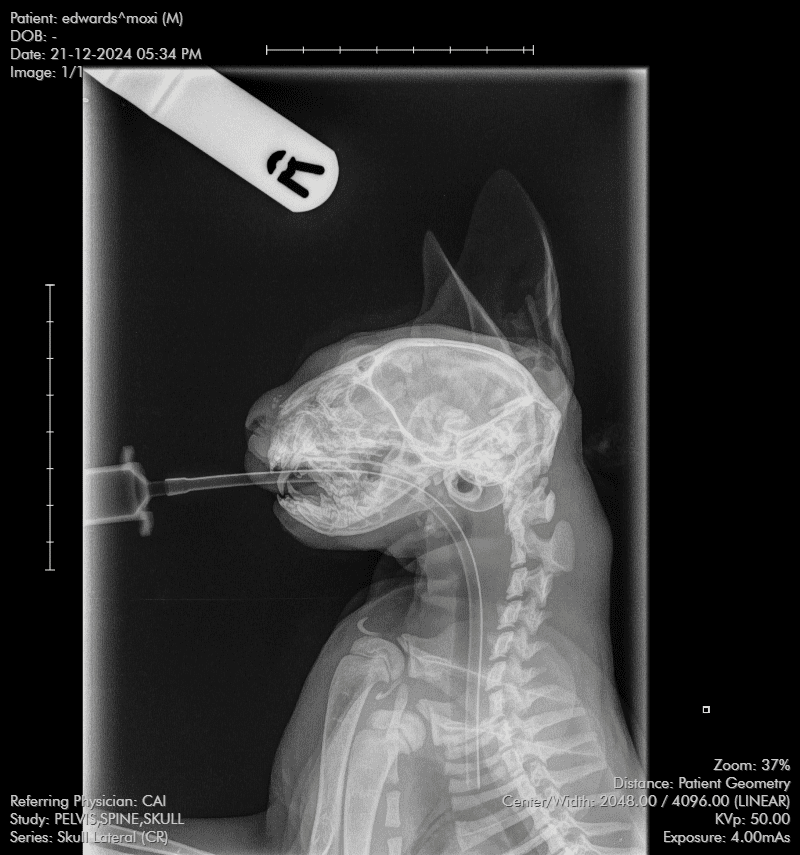

The court heard how the RSPCA started an investigation after Inspector Simon Evans attended the PDSA clinic in Cardiff on December 24, 2024 when he was shown the four-month-old tabby kitten which Edwards had brought in four days earlier. X-rays showed the feline had bony damage to the front of his skull and there were a number of older fractures/dislocations to his tail. The kitten’s lip was split and there was an injury to the right eye along with swollen genitalia.